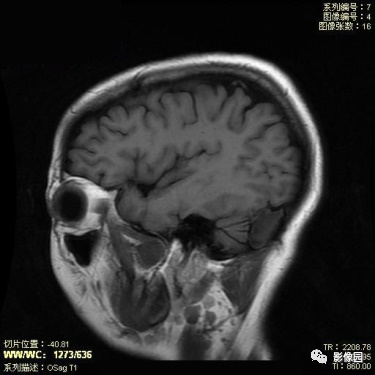

表皮样囊肿

【基本资料】患者,女,45岁

【主诉】发现颅内占位1月

【影像图片】